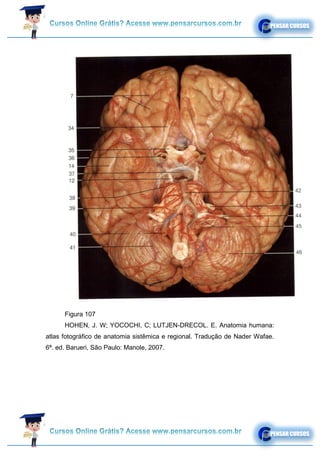

Figura 107

HOHEN, J. W; YOCOCHI, C; LUTJEN-DRECOL. E. Anatomia humana:

atlas fotográfico de anatomia sistêmica e regional. Tradução de Nader Wafae.

6ª. ed. Barueri, São Paulo: Manole, 2007.